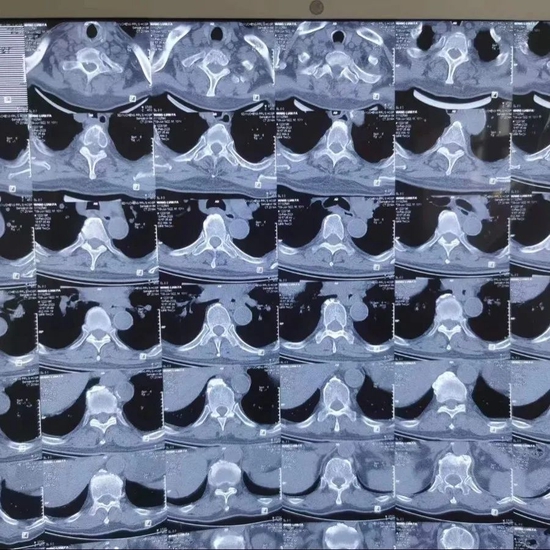

术前影像图片

该患者因后背部疼痛2个月入院,行胸椎CT检查显示,患者的T3椎体及其附件骨骨质破坏,食管(胸部下段)管壁增厚并纵隔,腹腔淋巴结肿大。结合放疗病房王兴主任的会诊意见,考虑老人出现的食管肿瘤合并淋巴结及骨转移并伴随T3椎体严重破坏,极容易发生骨不良事件,也就是T3椎体塌陷,老人出现高位截瘫。